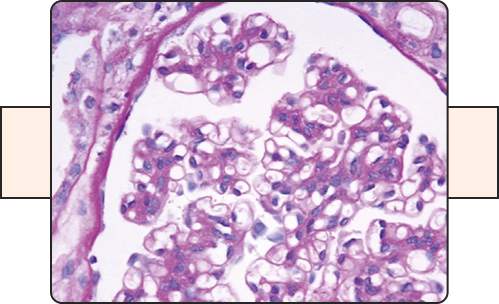

FSGS (Focal Segmental Glomerulosclerosis)

This Protocol will evaluate the efficacy of an investigational medication, in addition to evidence/based standard of care therapy aiming to reduce proteinuria and delaying the progression of kidney disease.